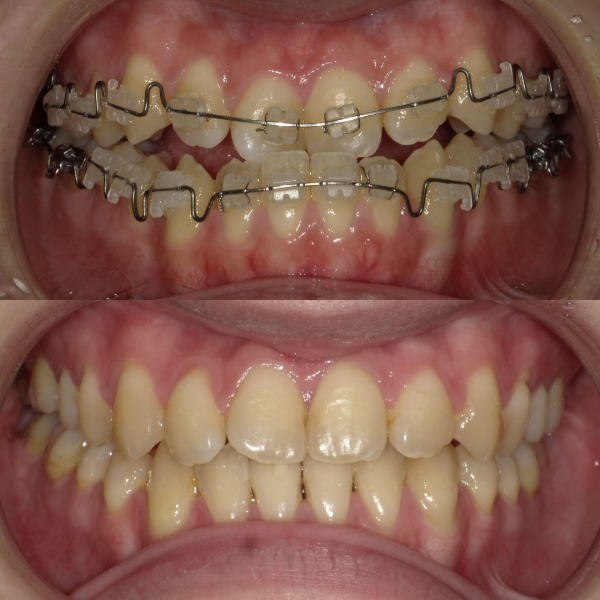

また、下顎の位置関係、歯の傾きなどの原因を新素材ゴムメタルワイヤーで治療を行うことでほとんどの症例で小臼歯を抜歯しなくても治療可能になってきています。